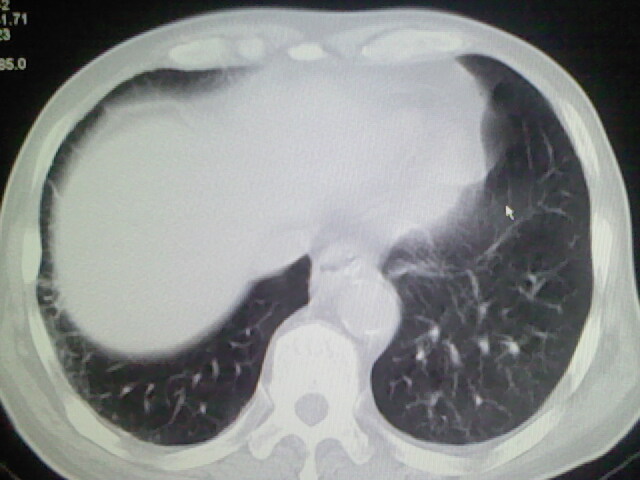

男,70岁,脑出血,长期卧床,左侧背部可触及肿块

右侧肺部见片状密度增高影,边缘模糊。考虑炎症。另食管壁增厚。

右肺上叶前段病呈楔形,其尖端指向肺门,考虑肺动脉栓塞可能性大.

肺部感染,背部筋膜增厚,考虑坠积性水肿或炎症